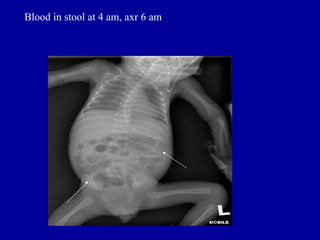

Blood in stool at 4 am, axr 6 am

Blood in stoolat 4 am, axr 6 am